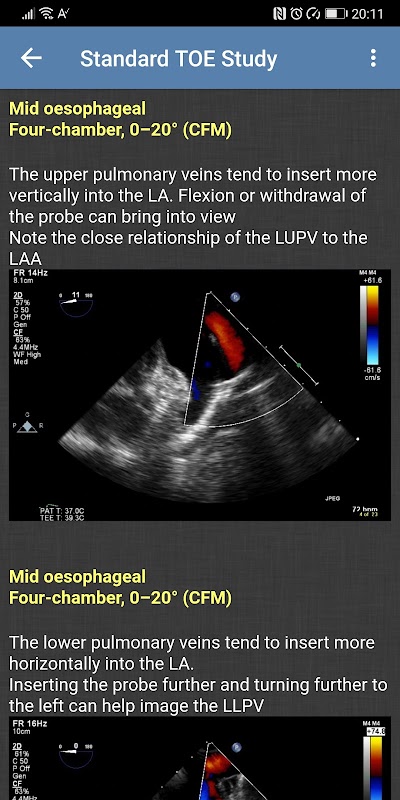

- Standaard TOE-onderzoek